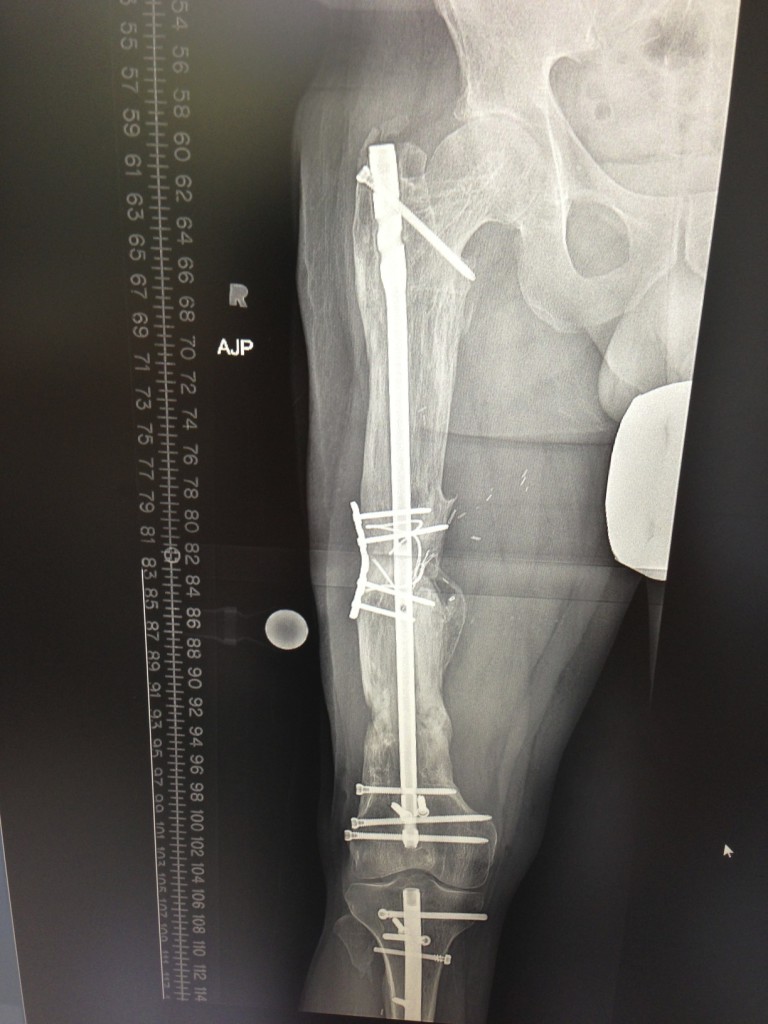

Ten years ago, I was diagnosed with Osteosarcoma in my right Femur bone. Although I have been very fortunate to have remained cancer free, the loss of 21cm of my femur had plagued me with a series of series of limb salvage attempts that continued over the course of six years. During this time, my leg was virtually unusable and I was experiencing chronic pain. It was determined that a low-grade infection was causing the bone to fail to mend with the donor bone that was placed to fill the void where the shaft of my femur once existed. After a number of consults with other physicians who recommended a procedure called a rotationplasty which is a partial amputation, or a total metal femur which has a highly reduced level of function, it was recommended I consult Dr. Rozbruch at HSS about limb lengthening. utilizing an Ilizarov external fixator, Dr. Rozbruch was able to grow my own healthy bone to fill the gap where the femur bone was missing. This left me with my own, healthy, natural bone with 100% recovery to the condition prior to being diagnosed with Cancer.

I have always led an active lifestyle with running, cycling, hiking, skiing, waterskiing, you name it. After a number of years of having no idea of the long-term condition that i am going to have to come to terms with in my leg, I am ecstatic to have resumed the life i once lived before this happened and I have to thank Dr. Rozbruch and his team for all the effort they put in. To say that this limb lengthening process is without complications or surprises along the way would be a bit misleading. In spite of this, Dr. Rozbruch handled every minor issue that came up with full confidence as it were simple routine. Even after bone defect was healed, Dr. Rozbruch was not satisfied with the outcome as the affected leg was still 3cm shorter than the "good" leg. Using a novel new internal fixator, he was able to lengthen the tibia (lower) bone of my leg by 3cm and I now have two fully-functional legs that are the same size. While undergoing these treatments, Sean Rose in the HSS physical therapy department was instrumental in helping me regain strength and balance that were lacking from 8 years irregular use.